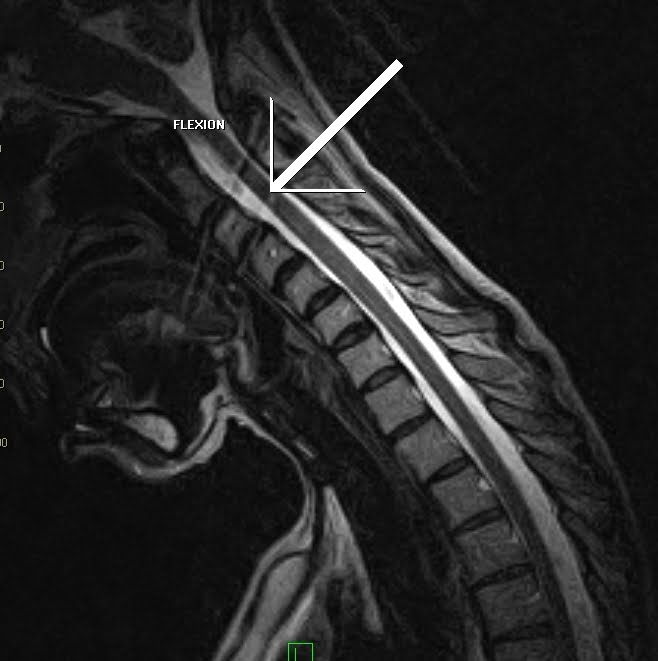

Flexion Extension Cervical Mri . Flexion and extension mri of the cervical spine can be used to evaluate isolated cervical spinal cord lesions seen on static mri. The potential importance of flexion/extension mri in the elucidation of cervical cord compression. Dynamic mri will show the flexional and extensional position of cervical spine other than neutral position.

Flexion & Extension Cervical MRI Sumer's Radiology Blog